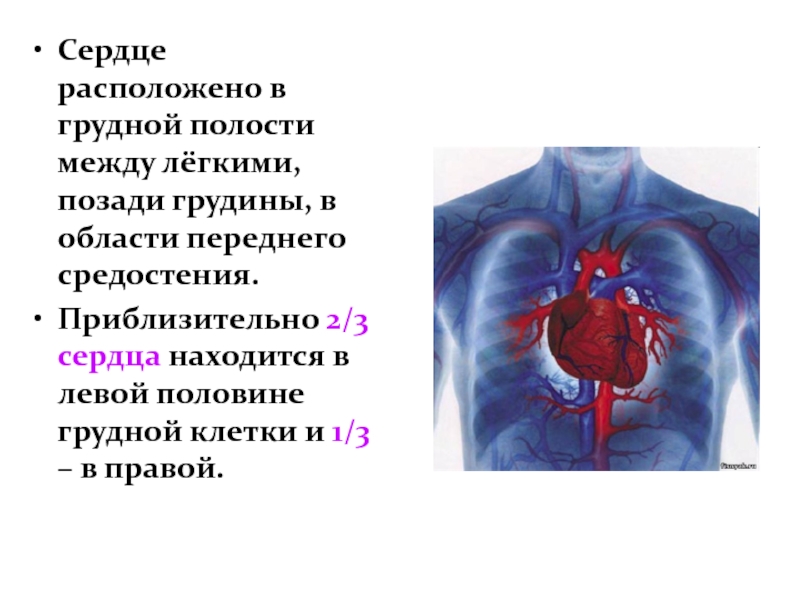

Анатомия Сердца: Расположение и Функции